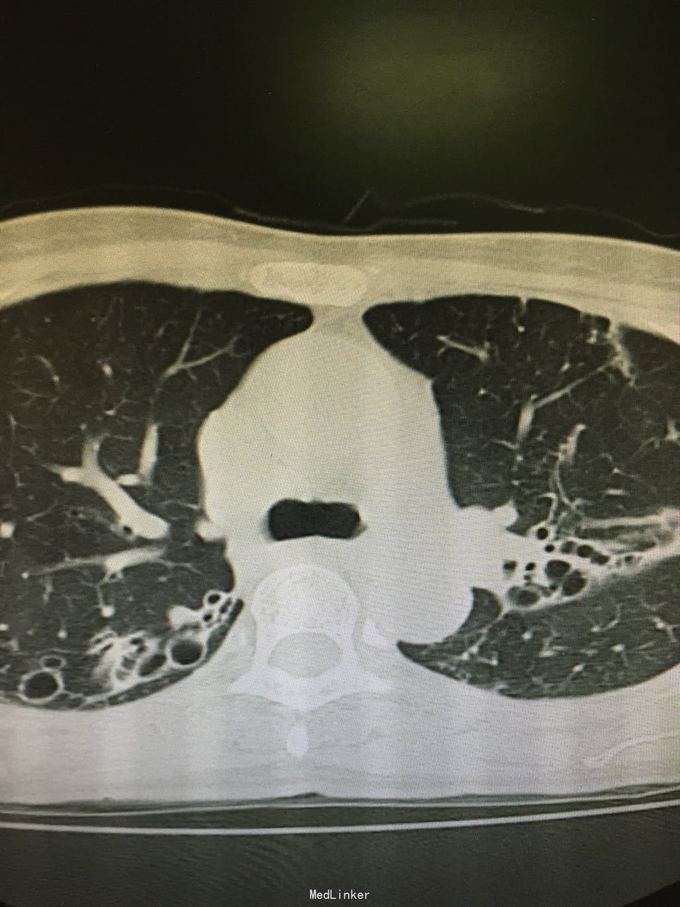

63岁女性,因“反复咳嗽、咳痰5年,加重1年”入院。

查体:双肺呼吸音粗,双上肺可闻及哮鸣音,双下肺可闻及干湿性罗音。外院胸片示两上中肺可见片装阴影,密度不均匀,边缘模糊,左中肺病灶中可见一椭圆形透光区,大小1.5*2.0cm;双肺纹理增粗、紊乱。考虑继发性肺结核(III上/上中。进展)我院胸片考虑支气管扩张。

诊断:支气管扩张并感染;肺结核?。入院后予甲磺酸左氧氟沙星200mlQd静滴治疗。

肺结核患者易并发支气管扩张。该患者影像学表现为碎饼干渣样,为较典型结核播散灶。支气管扩张表现也较典型。